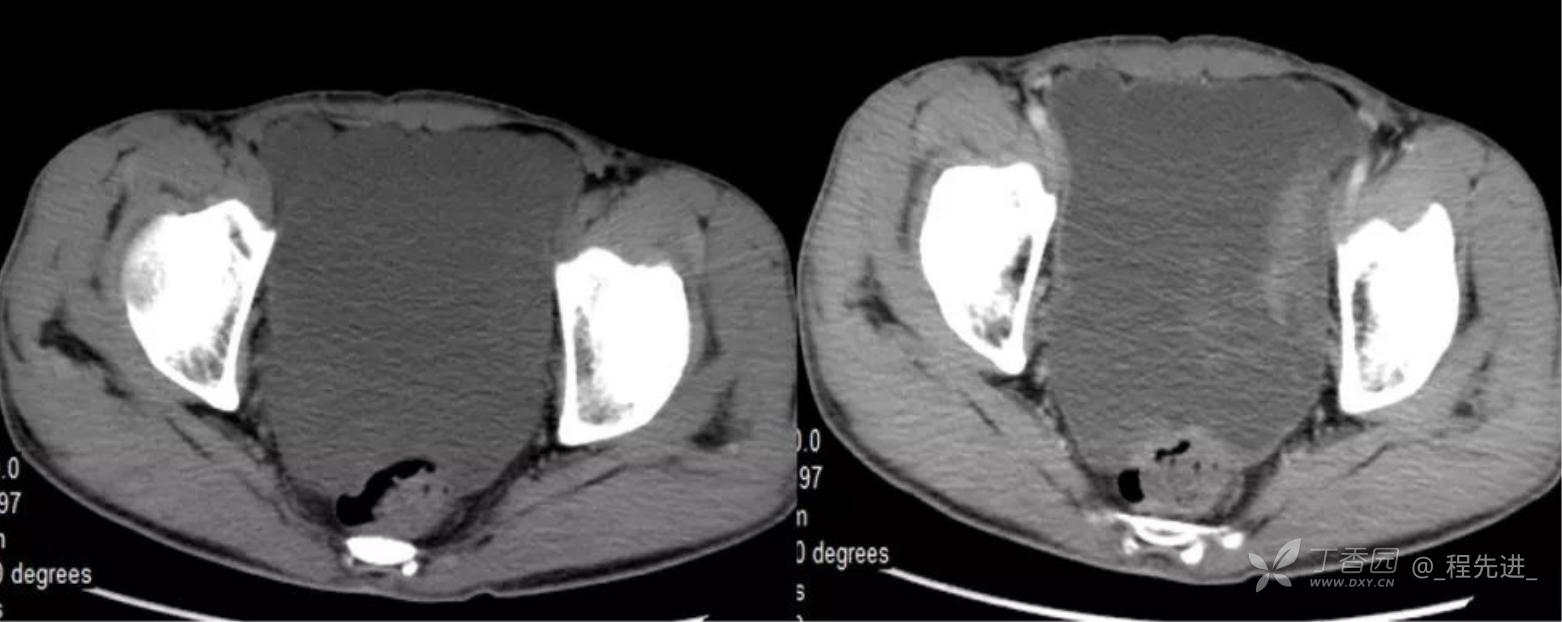

患者性别:男

患者年龄:46岁

主诉:腹胀10余天

现病史:患者10余天前无诱因腹胀,进食后加重,便后缓解,余无特殊

腹膜假黏液瘤 (5)